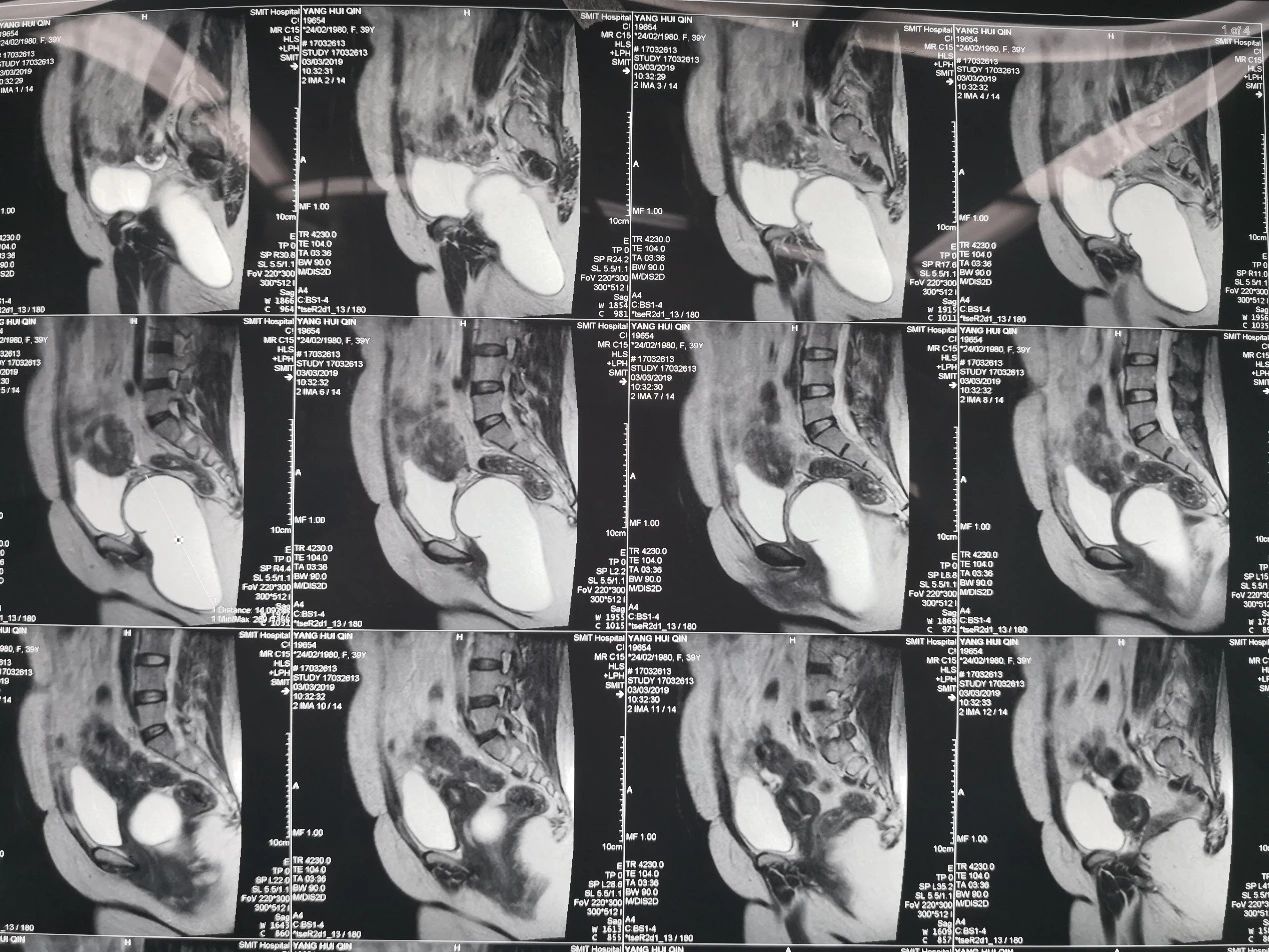

今天来应山西省新绛县人民医院梁主任邀请,行骶前囊肿切除。谈谈俯卧位,截石位的区别

俯卧位的优势是暴露尾骨周围组织很容易。缺点是骶骨后操作不能太深,如果骶前出血,很难暴露出血点止血,也不能与腹部操作相结合。适合比较浅的骶前囊肿切除。截石位优点是可以操作很深,直到腹膜返折处,骶前出血,容易暴露止血。截石位缺点是暴露尾骨周围比较困难,感觉创面很深,需要拉钩给力。优点是可以操作很深,直到腹膜返折处,骶前出血,容易暴露止血。适合位置深,多次复发的患者。今天该患者位置深,选取了截石位。